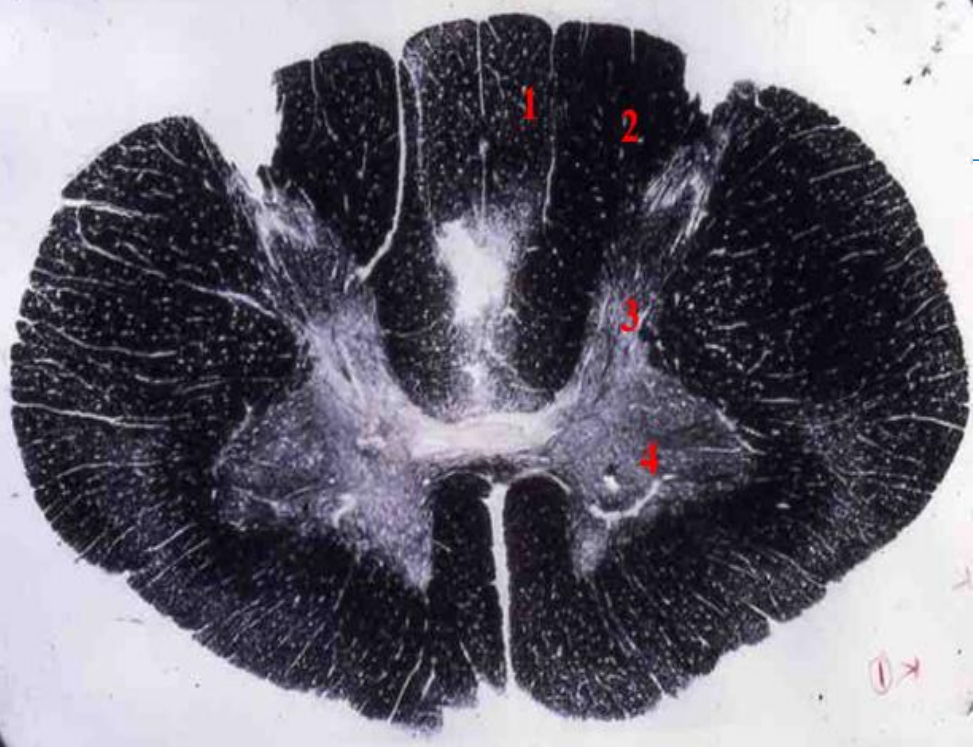

11

Q

indentify the weigert

A

cervical cord

- fibre tracts are larger

- grey matter is large

- brachial plexus

- no lateral horn

12

1

fasiculus gracilis

13

2

fasciculus cuneatus

14

3

posterior horn

15

4

anterior horn